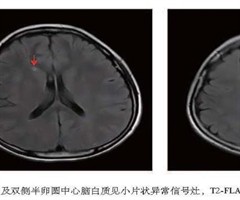

系统性红斑狼疮合并舞蹈症一例并文献复习

摘要:系统性红斑狼疮合并舞蹈症在国内相对罕见,目前尚无统一的诊断标准及特异性辅助检查,为排除性临床诊断。本文报道暨南大学附属第一医院风湿免疫科2022年1月收治的1例系统性红斑狼疮合并舞蹈症患者的临床资料,并结合近10年国内外相关文献进行复...